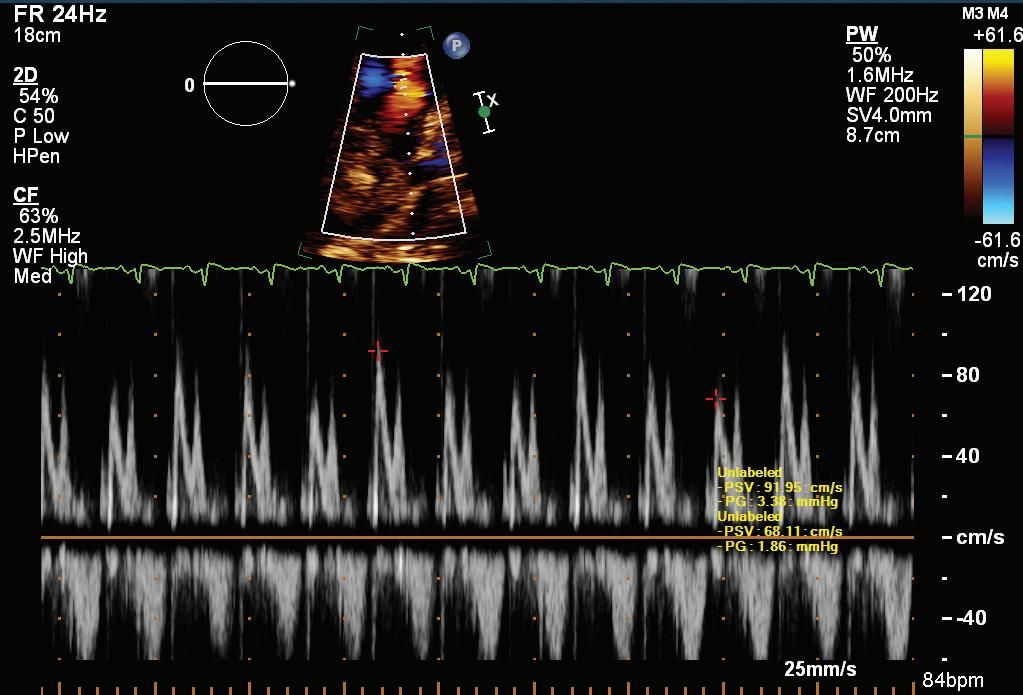

A 57-year-old man presented with a three-decade history of recurrent episodes of palpitation with alarming jugular venous pulsation, but without syncope. Each episode spontaneously reverted to the normal sinus rhythm 6–8 hours after the onset. Cardiac auscultation raised the suspicion of underlying rheumatic mitral stenosis. A 12-lead ECG was suggestive of a WPW pattern with a right posterior septal accessory pathway (Figure 1A). A chest X-ray in the posterior–anterior view was consistent with cardiac auscultation (Figure 1B). A transoesophageal echocardiogram confirmed rheumatic mitral stenosis (Figure 2A and Supplementary Material Video 1). The pliable mitral valve area was 0.8 cm2 and the mean gradient was 17 mmHg at a heart rate of 87 BPM. The coronary angiogram was normal.

On the day of the procedure, the first balloon mitral valvotomy was performed from a right femoral approach using a 23–26 mm Accura balloon (Vascular Concepts) after transeptal access using an 8 Fr SL-1 sheath and a BRK-0 needle (St Jude Medical). A transeptal puncture was performed after proper needle tip position was confirmed by fluoroscopy (right anterior oblique, left anterior oblique and 90° lateral views) and transoesophageal echocardiography (bicaval and short axis views; Figure 3A). The mean left atrial pressure prior to the valvotomy was 31 mmHg. The balloon was inflated to 26 mm in the right anterior oblique 20° position under fluoroscopy (Figure 3B) because the patient was 160 cm tall. The mitral valve area increased to 2.2 cm2 without any additional mitral regurgitation, and the mean left atrial pressure decreased to 12 mmHg without any mitral valve gradient. Immediate transthoracic echocardiography showed that the mitral valve gradient had decreased to 7/2 mmHg with negligible mitral regurgitation.

side and a horizontal left bronchus. A: There was significant mitral stenosis and the mean mitral valve gradient of 16 mmHg prior to the balloon mitral valvotomy. B: Atrial flutter with 2:1 atrioventricular block and right bundle branch aberrancy was evident during the electrophysiological study by pacing the atria with a decapolar catheter in the coronary sinus at cycle length of 200 ms.